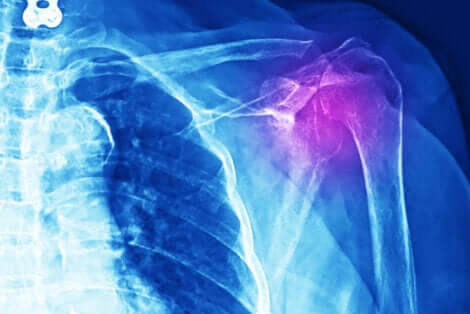

En outre, différents examens sont effectués pour diagnostiquer cette blessure : radiographie, écographie, IRM et même tomographie axiale calculée par ordinateur (TAC). On procède aussi à une reconnaissance médicale et à l’étude détaillée des antécédents cliniques du patient.

Les études d’images apportent des données importantes pour évaluer la gravité de la tendinite de l’épaule.